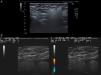

A, Kidney-shaped hyperechoic image in the subcutaneous cellular tissue with a homogeneous echostructure, a sharp upper border and sides, and a loss of the lower border due to the “snowstorm” artifact. B, Two adjacent hyperechoic images pseudoencapsulated in a “snowstorm” pattern in the subcutaneous tissue. Color Doppler imaging shows no vascularization.

The patient was a 46-year-old woman with a history of AJCC stage IB dorsal melanoma on the left side in 2013. A palpable subcutaneous mass of elastic consistency, approximately 4cm in diameter, was detected in the left axillar region during follow-up. On the basis of a suspicion of lipoma, an ultrasound was carried out (Esaote MyLab 25, 10MHz linear probe). The ultrasound revealed a diffuse hyperechoic image with a “snowstorm” pattern in the subcutaneous tissue, with a maximum diameter of 5cm (Fig. 1B). The patient confirmed having received PIP implants in 2002. She underwent a magnetic resonance imaging (MRI) study of the breast, which revealed a capsular rupture of the left breast implant and silicone granulomas in the axilla and around the implant (Fig. 3).